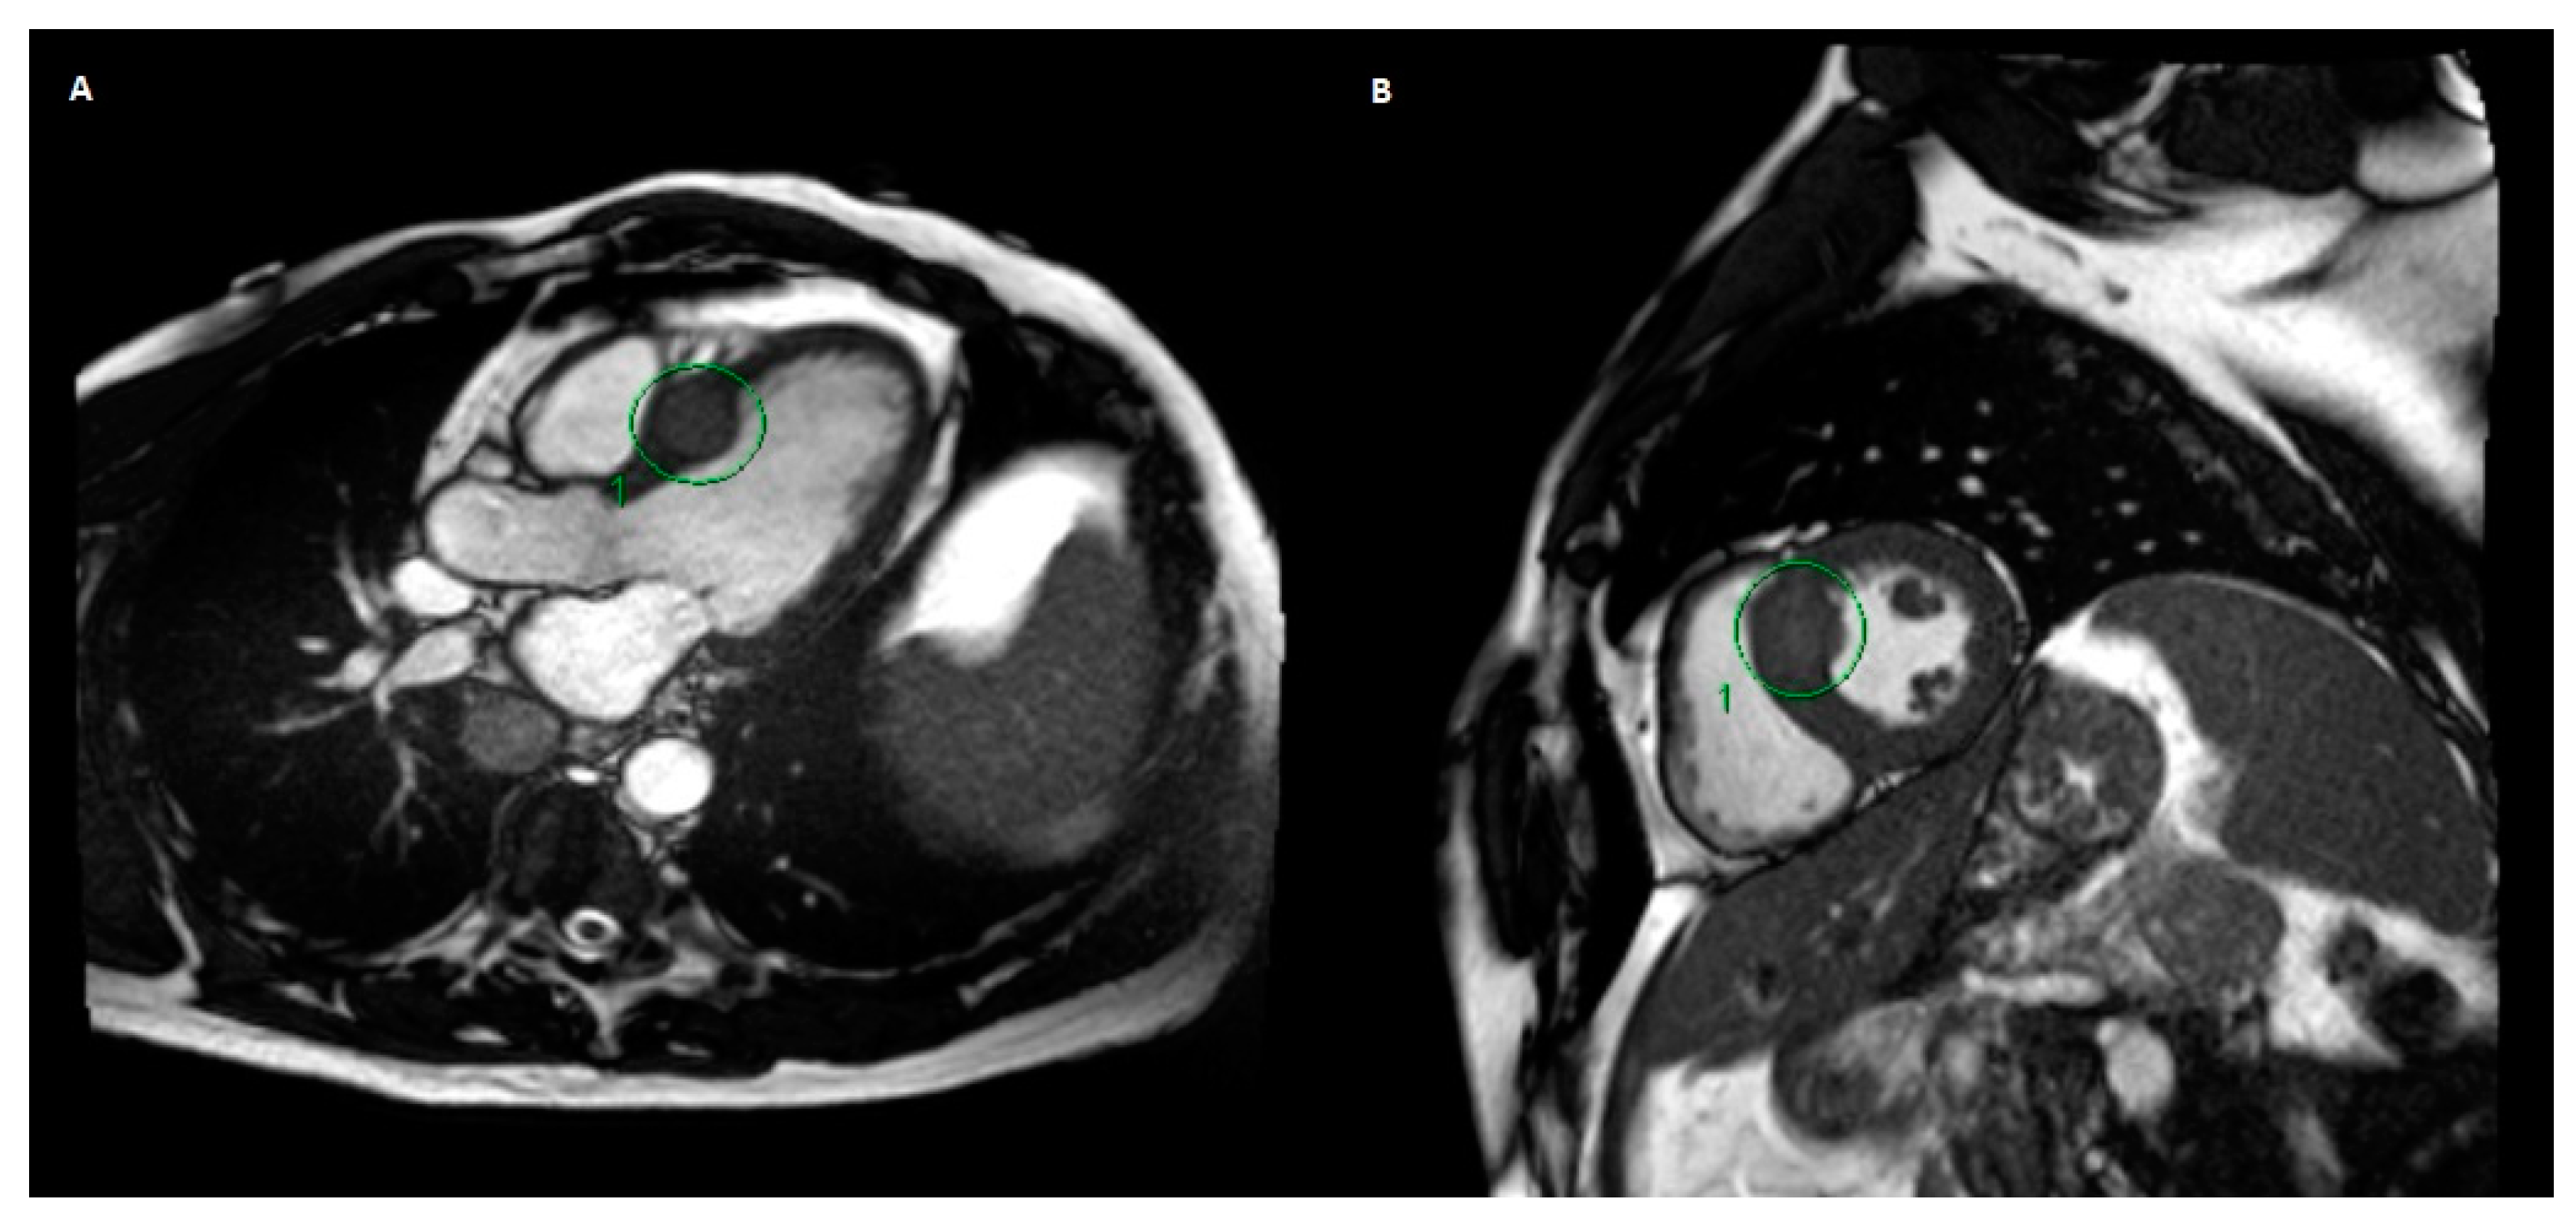

This patient then presented with a one-week history of shortness of breath, palpitations and presyncopal symptoms. A physical examination revealed an irregularly irregular rhythm on auscultation. An electrocardiogram (ECG) showed multiple ventricular ectopic beats. The patient was sent to the emergency department to have an urgent cardiology consultation to rule out an immunotherapy-mediated myocarditis. He was admitted in hospital and was monitored with telemetry. Bloodwork and serum troponin level were normal. Cardiac magnetic resonance imaging (MRI) showed a 2.8-cm metastatic lesion within the myocardial septum (Figure 1). In retrospect, this was noted on CT imaging 18 months and a few weeks prior to the cardiac MRI, where the lesion measured 1.3 cm and 2.4 cm, respectively. Ultimately, this lesion was felt to be the aetiology of his symptoms.

Figure 1. Magnetic resonance imaging (MRI) of the thorax and upper abdomen using gadolinium contrast and cardiac gating. Images from left to right show axial (A) and sagittal (B) views of the metastatic myocardial septum lesion (circled) prior to any treatment.

In our case, the patient did have mild chest pain and dyspnoea on exertion, although these self-resolved without intervention. There was improvement of the ECG findings after beta blocker therapy was started in hospital, and this continued for the remainder of the patient’s life. The troponin level prior to SBRT was normal and was not repeated after SBRT. An echocardiogram after SBRT did not reveal the lesion. His cardiac-gated MRI done prior to and after SBRT showed stability of the lesion. CT imaging of the chest was also done before and after SBRT, but these did not show the lesion as clearly as the cardiac-gated MRI.

Another challenge in this case was the delineation of the tumour for SBRT planning. Cardiac gating was not possible on the MRI simulation scans. The assessment of cardiac muscular motion through the cardiac cycle was difficult on both CT and MRI. The cardiac-gated diagnostic MRI was helpful in assisting with tumour delineation; however, the lesion was contoured generously to ensure the treatment encompassed it. Nevertheless, we recommend utilising cardiac-gated MRI, if available, to assist with delineating cardiac lesions during SBRT planning.